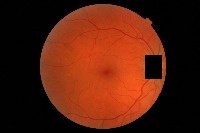

hard-exudate-detection1 Computer Vision Project

Diabetes Retinopathy Diagnosis: Medical professionals could use hard-exudate-detection1 to identify diabetic retinopathy in patients during routine screenings or for diagnosing symptoms, as hard exudates are a typical sign of this medical condition.

Automated Retinal Image Analysis: The identification of hard exudates could provide crucial information for automatic retinal image analysis software. It would provide an extra tool for detailed assessment of retinal images, providing comprehensive and accurate results.